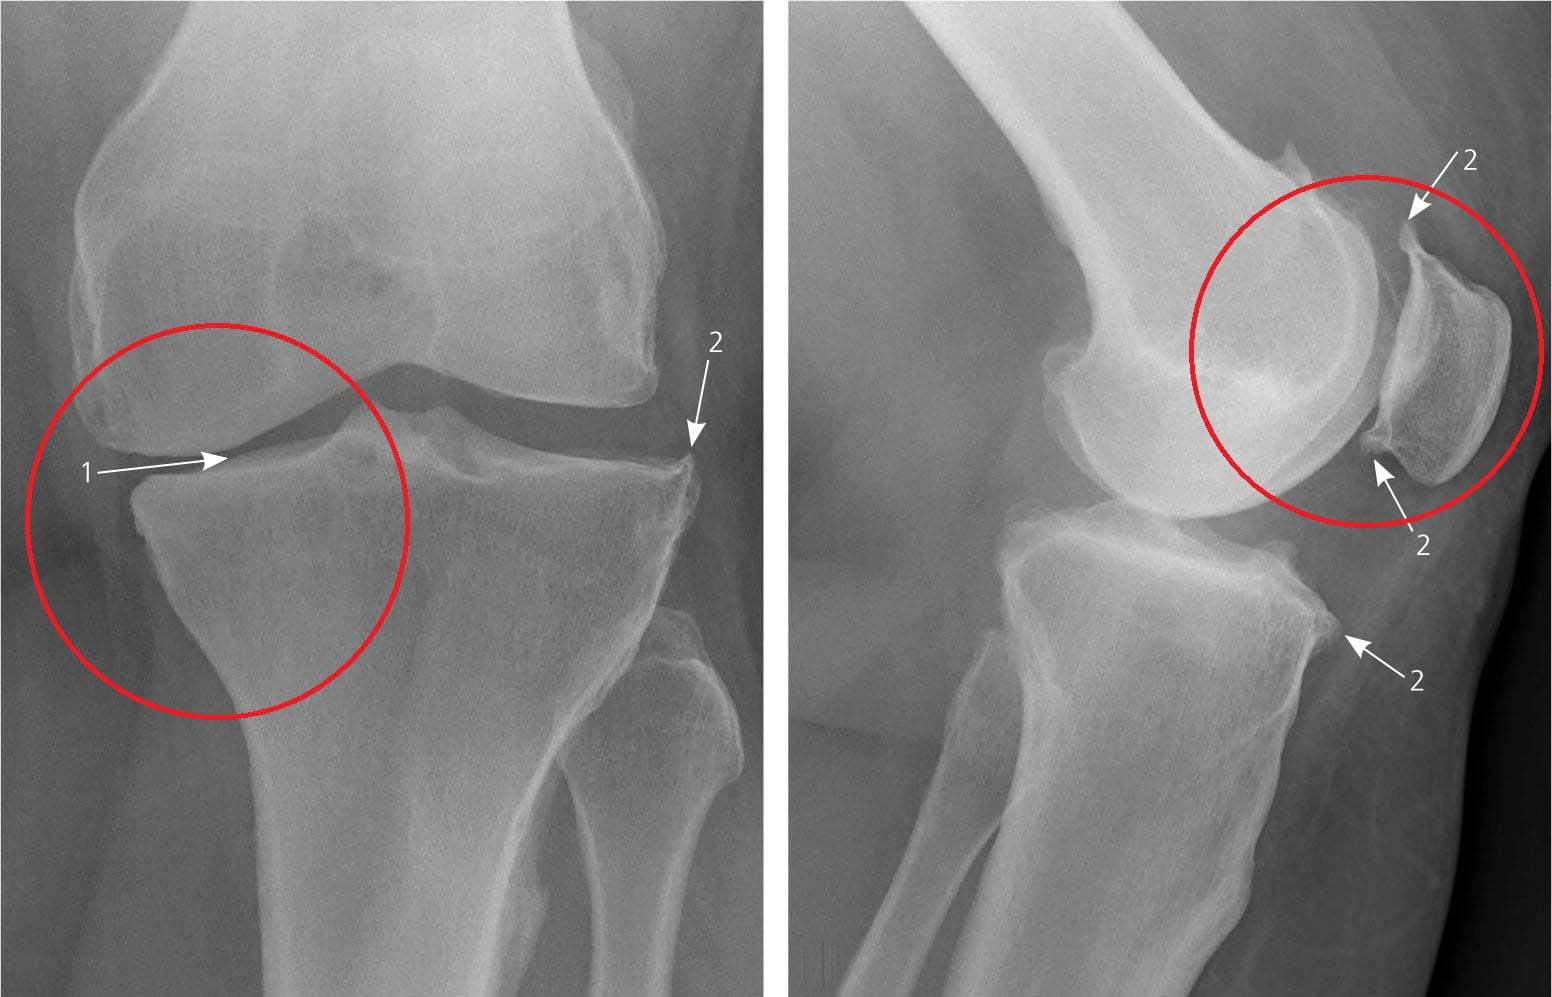

така се надявах... Без повече приказки ми направи пълен преглед, който включваше

рентгенови снимки и

изследвания на кръв и урина.

При следващото посещение, буквално в

рамките на няколко минути,

тя ми постави диагноза вторичен

остеоартрит с

усложнения. Честно казано, не разбирах какво точно казва. Обясни

направиха рентгенови снимки. Никакви признаци на остеоартрит! Хрущялите в

ставите ми бяха като на

20-годишно момиче. Лекарят реши, че предишната рентгенова снимка вероятно е била

с дефект, така че

диагнозата остеоартрит е била погрешна.